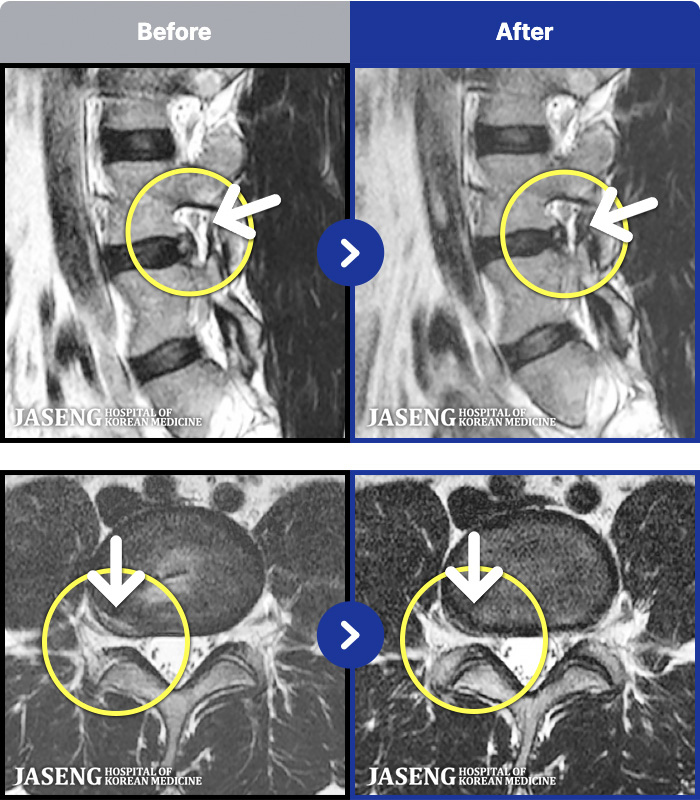

- MRI ġ

MRI ġ

1,237 MRI ũ ʸ Ȯϼ.